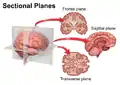

CT scan of the paranasal sinuses with coronal reconstruction (right) and axial planning data (left). Sectional Planes of the Brain

Sectional Planes of the Brain Identical twins at a gestational age of 15 weeks, shown in coronal and sagittal plane, respectively